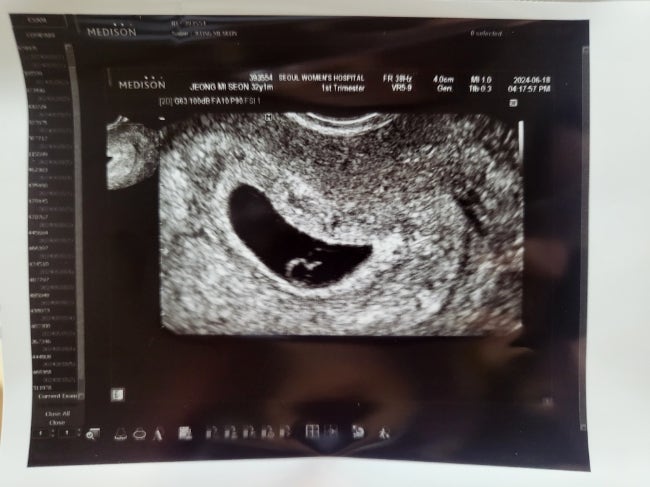

[임신 8주차 계류유산] 힘들었던 멘탈관리, 임신확인서없이 유산휴가와 유산바우처 신청

슬픈 일이긴하지만 털어내기 위해서 이 글을 남겨요 글이 길긴하겠지만 이것저것 검색하면서 걱정하는 분들...

[임신 초기 증상] 입덧에 좋은 음식! 임밍아웃 예정이었으나 유산하고 남기는 글

뽀짝이의 존재를 알게된 것은 6월11일 임밍아웃을 하려고 블로그에 글을 남기고있었는데 8주차에 유산을 하...